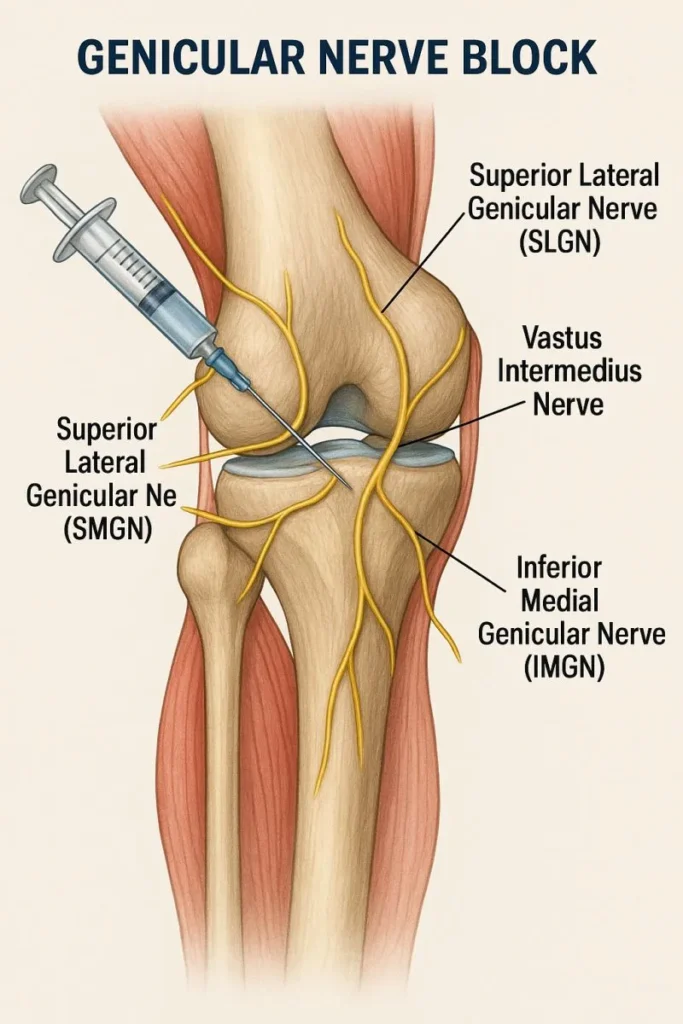

A genicular nerve block is not preparation given to the knee joint, which is more commonly known as an injection given to the knee joint. This procedure is intended to target the genicular nerves, which are very small and carry signals of pain from the joint to be relayed to the brain. The procedure involves very good knowledge of the area’s anatomy.

Genicular nerve block: This is a procedure for relieving knee pain through a minimally invasive method. Through genicular nerve block, a local anesthetic, as well as a tiny amount of anti-inflammatory drug if necessary, is administered close to particular nerves located around the knee region. The nerves transmit pain messages from the knee joint, particularly in cases of osteoarthritis, looking for the best genicular nerve block treatment in Jaipur.

“Pain from osteoarthritis of the knee is not one thing. Instead, it is a blend of processes: inflammation, joint wear, stiffness, and nerves transmitting painful signals.” A genicular nerve block is a precise targeting of a “nerve highway,” which is “the road your pain messages are taking.”

The practitioner finds the major SP sites around the knee region. Under the guidance of image intensification (usually fluoroscopy or ultrasound), a small needle is directed at the site around the SPs. A small quantity of local anesthetic is administered. This temporarily stops the transmission of pain signals.